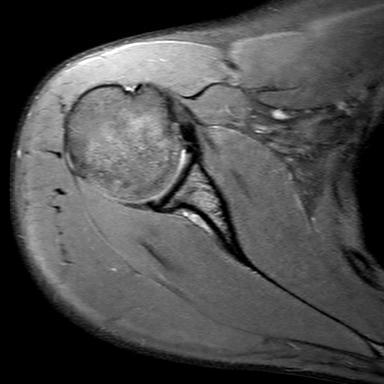

Ein Sehnenriss in der Schulter äußert sich meist durch heftige Schmerzen und teilweise mit Kraft- und Bewegungseinschränkungen. Häufig sind Sehnenrisse mit Engpassproblemen vergesellschaftet. Immer dann, wenn der dringende Verdacht auf einen Sehnenriss in der Schulter besteht (Rotatorenmanschettenriss oder Die positiv geladenen Wassermoleküle können magnetisiert werden, was sich das MRT der Schulter zu Nutze macht.

Ein Sehnenriss in der Schulter äußert sich meist durch heftige Schmerzen und teilweise mit Kraft- und Bewegungseinschränkungen.